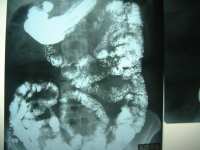

Barium Studies

What are barium studies?

These are studies of the gastro-intestinal performed using barium

sulphate and x-rays.

Why are there different types of barium studies?

Depending on the area being examined, we have barium swallow, meal,

meal-follow-through, enema and small bowel enema.

What are these?

Barium swallow is a study for the esophagus, barium meal for the

stomach, barium meal follow-through for the small bowel, barium enema

for the large bowel and small bowel enema for the small bowel. In

swallow, meal and meal-follow-through examinations, the patient has to

drink barium. In barium enema examinations, barium is injected using an

enema tube. In small bowel enema examinations (enteroclysis), a tube is

inserted from the nose to the duodenum and barium is injected.

How do barium examinations work?

Barium is an inert substance that coats the internal lining of the bowel

and fills up its lumen. It is radio-opaque and thus seen very well on

x-rays.

Barium Study - Enema Barium Study - Bowel Enema